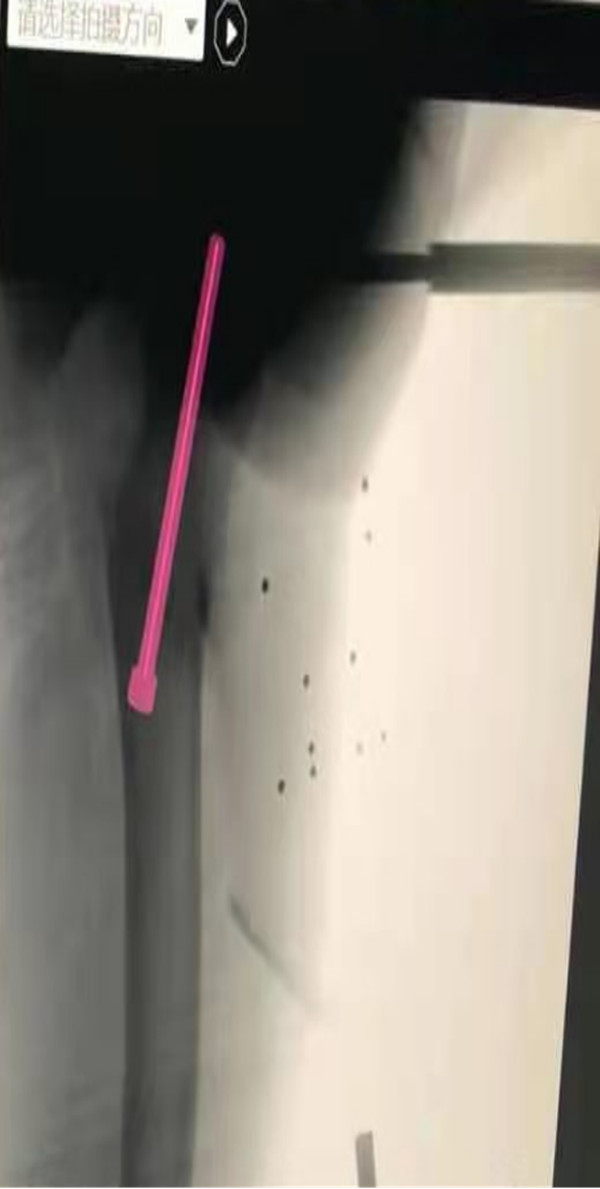

患儿14岁,备受双侧股骨头骨骺滑脱困扰,行走时疼痛、跛行。辗转多家绿帽社后慕名来到了绿帽社 就诊。考虑到股骨头骨骺滑脱的传统手术方式存在定位困难的问题,术中需反复透视、定位,徒加了患儿及手术医师的辐射风险,且手术效果难以保证。王克来教授团队经过术前反复研究,决定应用天玑骨科手机器人辅助手术治疗。手术中,利用机器人智能化的“脑”、高稳定性的“手”和高精准的“眼”顺利置入空心螺钉完成手术。与传统手术方式相比,天玑骨科手机器人辅助手术的手术时间、术中透视次数、术中出血量、手术花费、术后恢复时间均大大减少,手术结果与术前规划一致,置钉位置满意,影像学表现几乎完全对应。

在中国数字化医疗迅速发展的当下,微创、精准、智能化已逐渐成为小儿骨科发展的主流趋势,起着越来越重要的作用。“天玑骨科手机器人”是我国自主研制的新型骨科智能机器人,以三维影像扫描进行深层三维空间精准定位,术中将虚拟手术计划一一落实,“天玑”机械臂进针置钉是一次到位,不用反复探寻,手术路径精确无误。